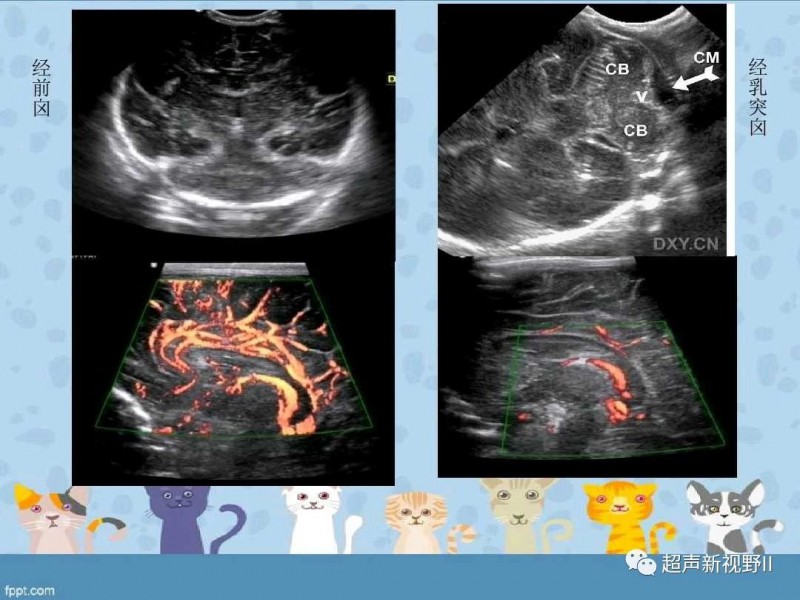

新聞中心 【超聲微課堂】新生兒顱腦超聲檢查規(guī)范